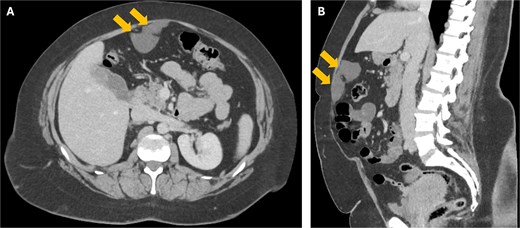

A 38-year-old woman presented to clinic with chronic supraumbilical abdominal pain. This was not associated with any gastrointestinal or constitutional symptoms, or systemic unwellness. She did not have any significant medical history. She had a Caesarean section 5 years prior. On examination, a large mass was palpated in the supraumbilical area; there was a small reducible fat-containing umbilical hernia, and there were no signs of peritonism. Blood tests including serum tumour markers were unremarkable. Computed tomography (CT) of the abdomen revealed an 8 × 3 cm hypodense lesion just deep to the anterior abdominal wall (Fig. 1). An ultrasound (USS) characterised this lesion as an 8 × 7 × 3 cm cyst with simple internal contents suggestive of a falciform ligament cyst (Fig. 2).

Axial (a) and coronal (b) CT images showing the 8 cm falciform ligament cyst (arrows) just deep to the anterior abdominal wall.